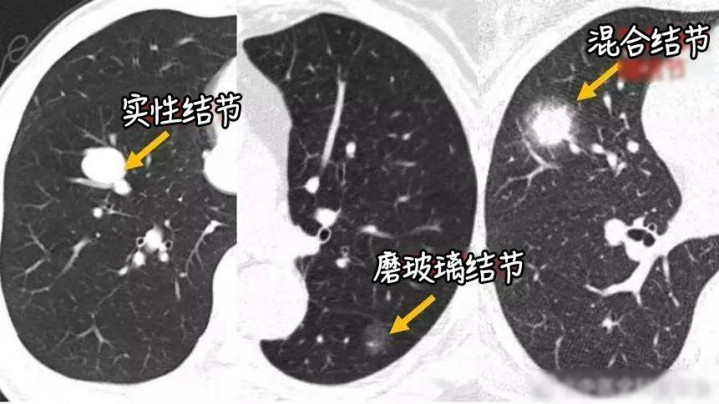

磨玻璃结节是肺结节的一种,临床上按照结节密度,主要分为三类:

1.纯磨玻璃结节:CT下炫耀为相对较黑的模式,里面仍有极少气体,形似被砂纸磨过的玻璃。它并非肺癌,一部分是短期炎症,经消炎诊治后可消退;少部分抓续存在的纯磨玻璃结节,多为惰性极强的早期病变,且其5年恶变率仅1.5%驾驭;

2. 搀杂磨玻璃结节:联系于纯磨玻璃结节而言,纯磨玻璃结节内无实性要素,而搀杂磨玻璃结节内含有一定比例的实性要素;

3.实性结节:肺部实性结节,病情走向不竭呈现南北极分化,或者可分为两种极点情况。一种是全皆良性,推行多为肺内淋夤缘增生,南昌期货配资或是既往炎症继承后留住的纤维瘢痕,以这类居多。另一种则是恶性过程较高的肿瘤,这类结节从发生之初就会慢慢充填肺泡,在影像上证据为纯实性结节,粗俗滋长速率较快,短期复查即可不雅察到显著增大的迹象,这类占少数。